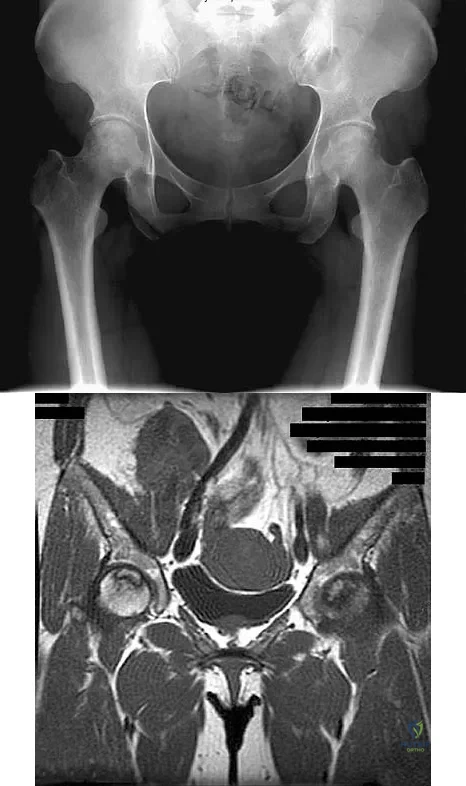

Question 47

A 46-year-old woman has bilateral groin pain, with more severe pain on the left side than on the right side. Figures 44a and 44b show a radiograph and a T1-weighted MRI scan. What is the most likely diagnosis?

Explanation